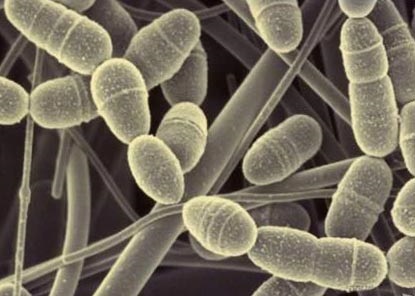

Fig. 11. Treponema denticola. Parazit în cavitatea bucală într-o persoană sănătoasă nu se manifestă. În anumite condiții, cauzează boli ale gingiilor.